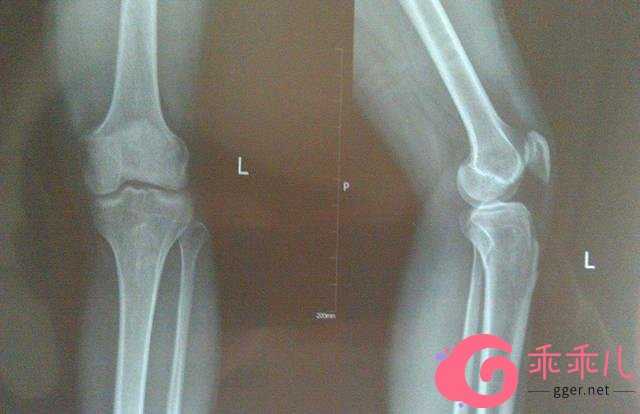

不幸的是,小刚以后的个子再也没长过,都20了才带着去看医生,医生诊断:骨骺缝已经闭合,无法用药物治疗了。